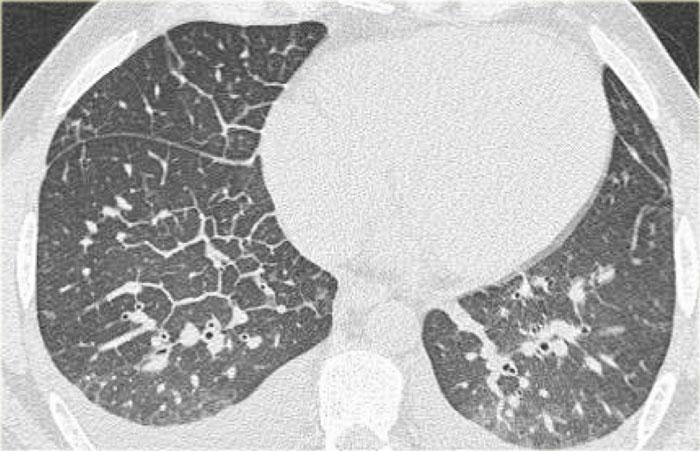

CT cũng có thể biểu hiện các dấu hiệu của suy tim sung huyết.

Trên hình ảnh bên trái, lưu ý các dấu hiệu sau:

- Đường vách dày lên do phù mô kẽ

- Mờ dạng kính mờ (ground glass) nhẹ ở phần phụ thuộc trọng lực của phổi (chênh lệch HU từ 100-150 giữa phần phụ thuộc và không phụ thuộc trọng lực của phổi).

- Tràn dịch màng phổi hai bên.

Ở bệnh nhân có tiền sử ác tính, ung thư biểu mô dạng viêm bạch mạch sẽ được xếp cao trong danh sách chẩn đoán phân biệt.

Mờ dạng kính mờ là biểu hiện đầu tiên của phù phế nang và là giai đoạn tiền thân của đông đặc.

Cả trên X-quang ngực lẫn trên CT, phù nề đều phụ thuộc vào trọng lực và sự chênh lệch tỷ trọng có thể được đo lường.

Lưu ý rằng ngay cả trong mỗi thùy phổi, cũng có sự chênh lệch tỷ trọng phụ thuộc trọng lực.

Điều này chỉ được thấy khi các đông đặc là kết quả của dịch thấm như trong suy tim sung huyết.

Điều này không được thấy khi các đông đặc là kết quả của dịch tiết do nhiễm trùng, máu do xuất huyết, hoặc khi có rò rỉ mao mạch như trong hội chứng suy hô hấp cấp tiến triển (ARDS).